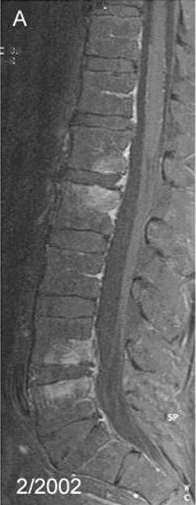

Spondylitis due to Tropheryma whipplei. Contrast-enhanced, T1 weighted fat suppressed magnetic resonance imaging demonstrating contrast enhancing lesions of spondylitis in the first (L1) and second (L2) as well as fourth (L4) and fifth (L5) lumbar vertebra, sparing the intervertebral discs.